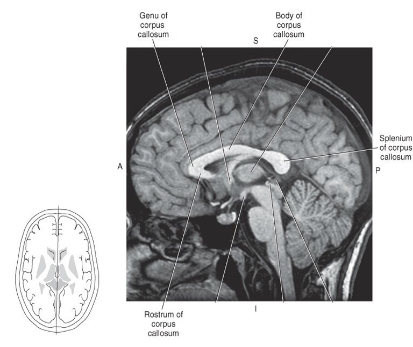

What is the Corpus Callosum and what is its function?

An important commissural tract connecting the two cerebral hemispheres, containing rostrum, genu, body, and splenium.

What are the four parts of the corpus callosum?

Rostrum, Genu, Body, Splenium.